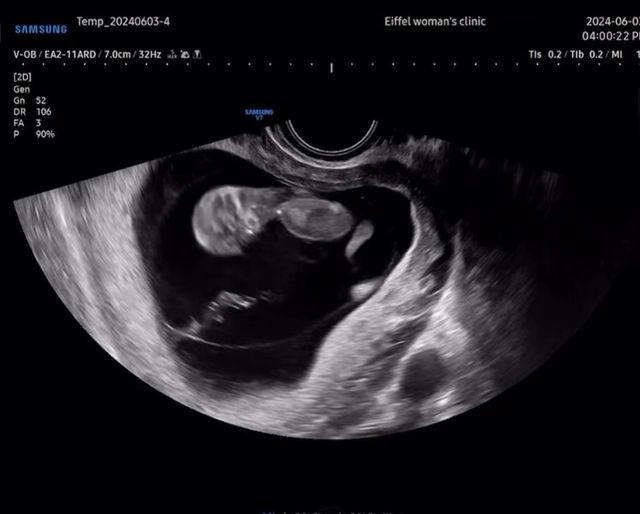

(엑스포츠뉴스 오승현 기자) 배우 류시원이 19살 차 아내의 임신소식을 전한 가운데, 직접 아기의 사진을 공개했다.

4일 류시원은 "기쁜소식이 있어 조심스레 알려드려요~^^"라는 글과 함께 초음파 영상과 사진을 게재했다.

공개된 사진에는 활발하게 움직이는 태아의 모습이 그대로 담겨 귀여움을 안긴다.

류시원은 "낼모레면 12주차, 크기는 이미 12주차"라며 애정을 여실히 드러냈다.